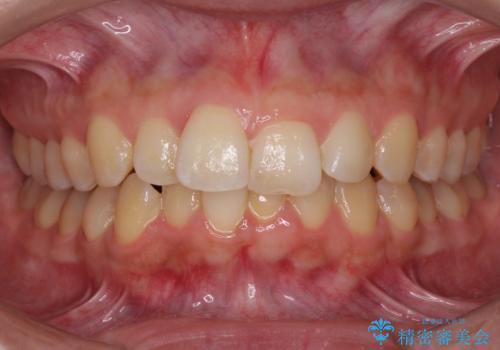

[ マウスピース矯正 ] がたがたした歯並びを治したい

担当医 大元洋佑